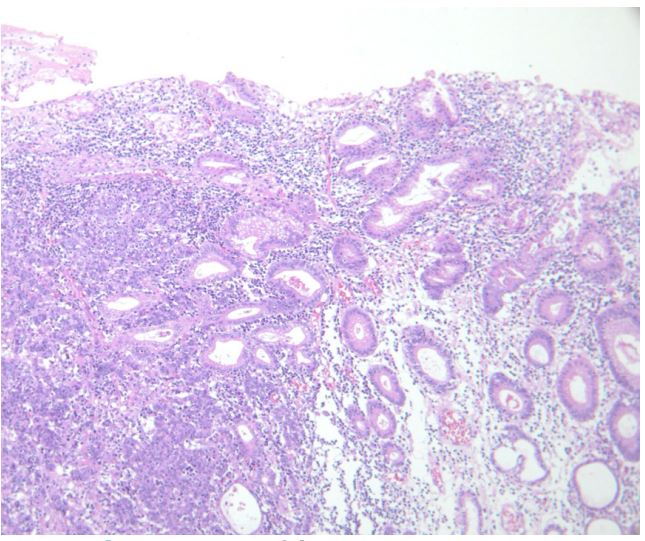

Figure 3b: H&E image of the primary gastric cancer

Figure 3c,d: Invasion of the gastric cancer to the transverse colon (c), pancreas (d).

An eighty-year-old woman presented with the symptoms of abdominal pain, slight fever of 37-38°C, and body weight loss. Upper Gastrointestinal (GI) examination performed one month prior to presentation revealed a gastric tumor, while Esophagogastroduodenoscopy (EGD) showed a type 3 tumor in the gastric fundus and corpus (Figure 1a). However, food residues covering the tumor surface prevented precise observation. Colonoscopy revealed an irregular surface elevation in the splenic flexure of the colon (Figure 1b), in which an adenocarcinoma was detected by biopsy. Contrast-enhanced computed tomography (eCT) revealed advanced GC with extensive invasion of the transverse colon, spleen, and pancreas (Figure 2a,b). Peritoneal dissemination and lymph node metastasis were suspected. The eCT image also showed gas in the pancreatic duct, indicating fistulation from the stomach to the pancreatic duct due to tumor invasion (Figure 2b). This fistula was presumed to be the cause of the patient’s low-grade fever. Thus, relatively rapid surgery was performed to control bacterial infection of the pancreatic duct and ensure resection of the advanced GC. Open surgery was performed, and extensive invasion of the GC into the pancreas and transverse to the descending colon was detected. Fortunately, no obvious peritoneal dissemination was observed. Therefore, a total gastrectomy with D2 lymphadenectomy combined with distal pancreatectomy, partial colectomy, and cholecystectomy was performed. Cholecystectomy was added as it is performed along with total gastrectomy as the standard procedure in our institute. The resected gastric tumor measured 160×80 mm (Figure 3a). Pathological tests revealed a poorly differentiated adenocarcinoma of the stomach invading the pancreas, transverse colon, and splenic serosa (Figure 3b-e). No metastasis was identified in the dissected lymph nodes or peritoneum. The pathological cancer stage was IIIA, according to both the TNM Classification of Malignant Tumours-8th edition [13] and the 15th edition of the Japanese Classification of Gastric Carcinoma[14]. Approximately two months after surgery, we initiated adjuvant chemotherapy with tegafur/gimeracil/oteracil, which was discontinued after only two months due to severe adverse events. Two years after surgery, the patient remains alive without relapse.